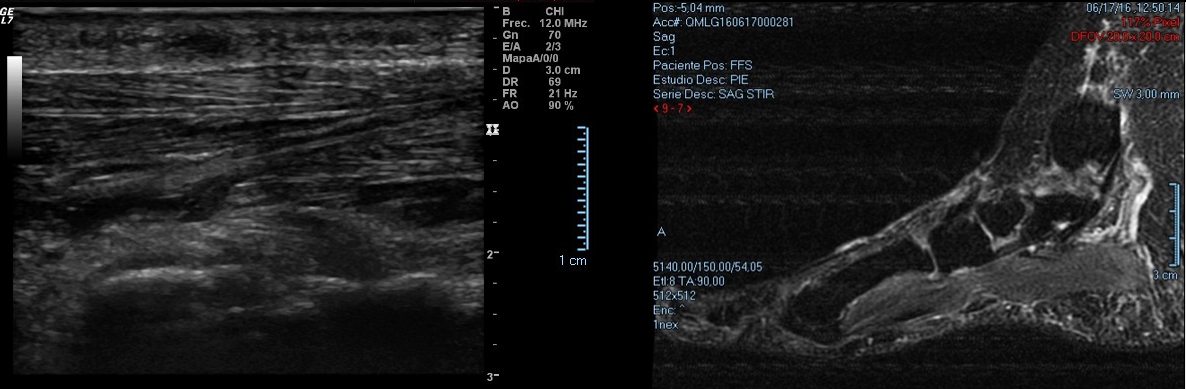

En general se pueden diagnosticar mediante la exploración clínica y una correcta anamnesis. A su vez nos apoyaremos en ecografías o RMN para visualizar la masa fusiforme, delimitar el grosor y diferenciar estructuras afectadas. A nivel de la zona dolorosa se puede apreciar una formación fusiforme de 15 mm hipoecogénica adyacente a la fascia plantar.

El síntoma principal del fibroma plantar es la presencia de un bulto palpable en el arco del pie. En las primeras etapas, este nódulo puede ser pequeño y no causar molestias. Sin embargo, a medida que crece o si está ubicado en una zona de apoyo, puede generar dolor en el arco plantar y rigidez en la fascia plantar.